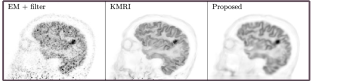

A 3D brain phantom from BrainWeb [31] was used in the simulation. Corresponding T1 weighted MR image was used as the prior image. The voxel size is 2×\times2×\times2 mm3superscriptmm3\mbox{mm}^{3} and the phantom image size is 128×\times128×\times105. To simulate mismatches between the MR and PET images, twelve hot spheres of diameter 16 mm were inserted into the PET image as tumor regions, which are not visible in the MR image. In this experiment, the last 5 min frame of a one-hour FDG scan was used as the ground-truth image. The computer simulation modeled the geometry of a Siemens mCT scanner. Noise-free sinogram data were generated by forward-projecting the ground-truth image using the system matrix and the attenuation map. Poisson noise was then introduced to the noise-free data by setting the total count level to be equivalent to last 5 min scan with 5 mCi injection. Gaussian post-filtering method (denoted as EM+filter) and the kernel method (denoted as KMRI) [12] were employed as comparison methods. Fig. 4 shows three orthogonal views of the reconstructed images using different methods. The kernel method and the proposed method both reveal more cortex structures compared to the EM-plus-filter method due to the boundary information provided by the MR priors. Compared to the kernel method, the proposed method can recover even more details of the cortices and the white matter regions are cleaner. Besides, the tumor uptake using the proposed method is higher and the tumor shape is closer to the ground truth. This means that even when there are mismatches between the PET and MR images, the proposed method can still recover the true PET intensities and shapes. Fig. 6(a,b) shows the contrast recovery coefficient(CRC). vs standard deviation (STD) curves for different methods. For both the gray matter region and the tumor region, the proposed method out-performs other methods.

Refer to caption

(a)

(b)

(c)

Figure 4: Three orthogonal slices of reconstructed images using different methods for the simulation brain dataset.